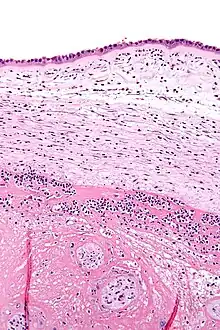

Histopathologie de la chorioamnionite. L'amnios (partie haute de l'image) présente des neutrophiles épars, ce qui permet de diagnostiquer une chorioamnionite.

Une chorioamniotite est une inflammation des membranes fœtales, l'amnios et le chorion, généralement causée par une infection bactérienne[1].